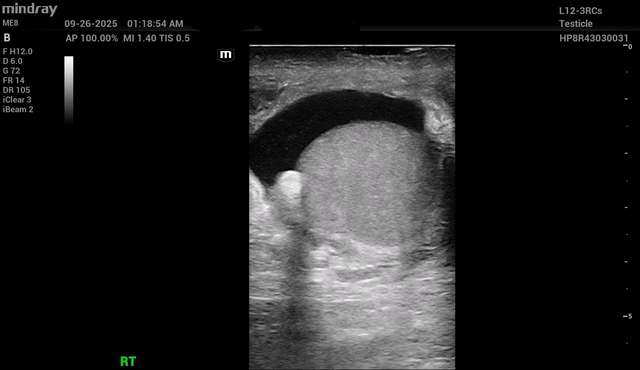

The Ball’s In Your Court: A Case of Testicular Rupture

Booth EMFebruary 23, 2026

Torsion

Booth EMOctober 15, 2025